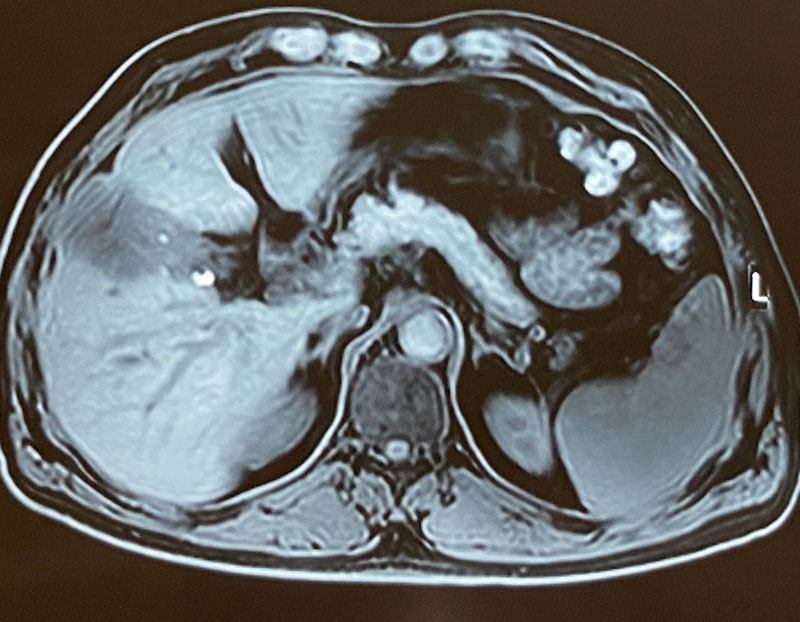

63 year old gentleman presented with right upper abdominal pain, loss of appetite, loss of weight & a USG report showing a gall bladder mass involving liver. Patient was thoroughly investigated. Investigations (PET-CT scan,MRI & tumor marker CA19-9 were highly in favour of a gall bladder cancer which could be completely removed. Hence immediate surgery was conducted without any preoperative biopsy to avoid any tumor spillage. An intraoperative controlled biopsy (Frozen section) confirmed the malignancy. The tumor was removed in toto along with portion of attached liver and draining lymph nodes. Patient recovered well in 5 days and was discharged. He was recommended postoperative chemotherapy based on the histopathology (adjuvant chemotherapy) A chemoport was inserted for the ease of delivering chemotherapy in a safe and painless manner. Patient was put on a strict follow up protocol.

1. It is vital that patient is properly investigated using PET-CT scan, MRI, Liver function tests & tumor marker CA19-9.

5. Operable and resectable patients may need (depending on the extent of disease) a radical cholecystectomy with or without liver resection / pancreatoduodenectomy / vascular resection with reconstruction and even some bowel resection.